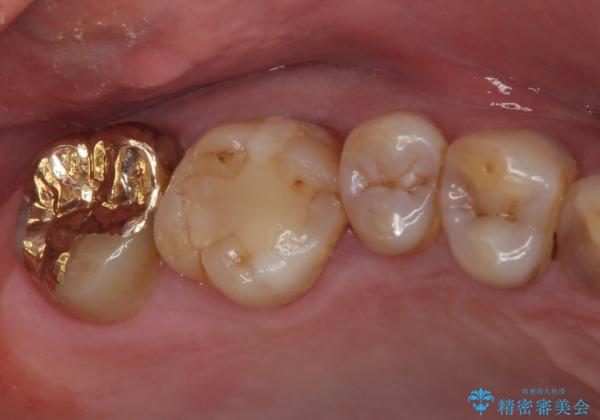

虫歯をしっかりと取り除き、ゴールドインレーにて修復することとしました。

ゴールドインレーは銀歯のインレーやセラミックインレーと比べ、「技工操作の精度が高く、適合が著しく良い」というメリットがあります。特に上の奥歯は歯科医師の操作が行いにくいため、「適合の良さ」は再治療のリスクを防ぐ上でとても重要な要素となります。

上の奥歯は金属色が見えることもないため、審美的な問題は全くありません。

咬み心地はとても良好で、全く違和感がなく、患者様には大変満足していただきました。